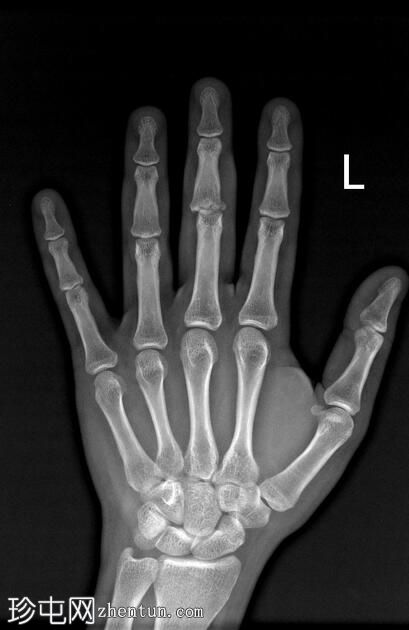

正位

可见第三指中节指骨基底部轻微移位骨折,延伸至近端指间关节(PIP关节),并伴有软组织肿胀。

第三指中节指骨基底部轻微移位骨折,延伸至近端指间关节(PIP关节)指骨,并伴有软组织肿胀。